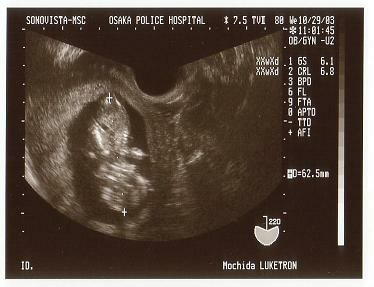

<第三回超音波検査>

10月29日、第3回目の超音波検査です。写真のキューピー

ちゃんみたいなのが俊介です。逆に見た方がわかりやすいかな。

完全に人間の形をしています。まだ家内のお腹は目立っており

ませんでしたが、このような写真をみると、私の心の中で、

「父親になるんだなぁ」って気持ちがどんどん強くなっていく

のを感じたことを覚えています。

この検査のときは画面上で実寸を測ってもらっております。

俊介の体長は6.25cmです。